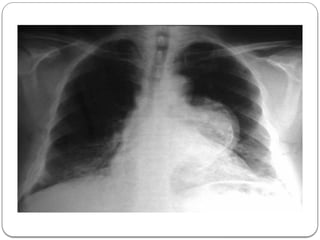

Chest X-Ray

• Abnormal aortic sillhouette

• Mediastinal mass  diffuse

widening mediastinum

• Enlargement aortic knob

• Tracheal deviation

• Change in aortic contour

Chest X-Ray • Abnormalaortic sillhouette • Mediastinal mass  diffuse widening mediastinum • Enlargement aortic knob • Tracheal deviation • Change in aortic contour